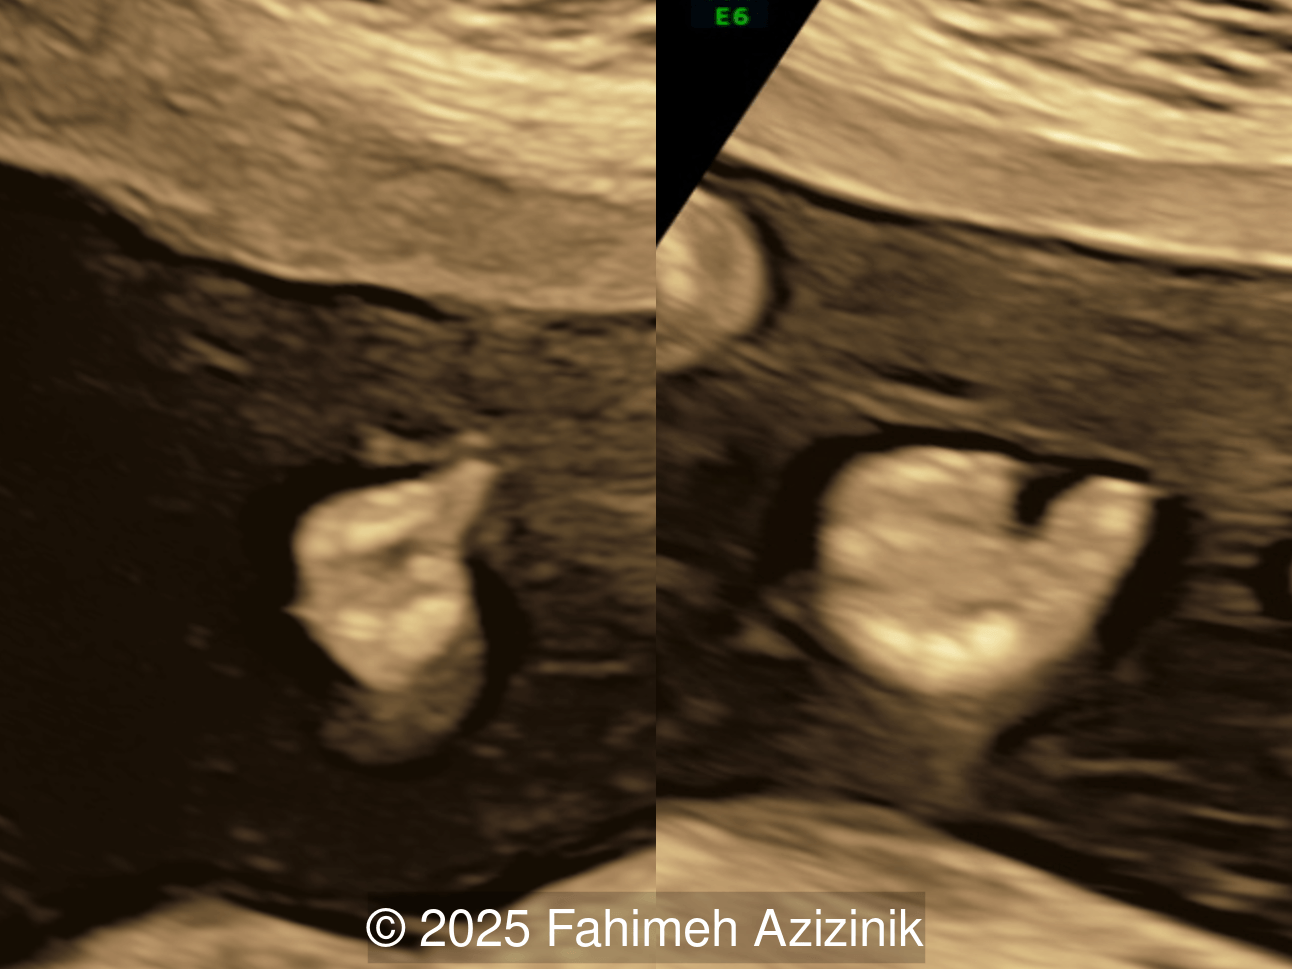

Image 1

Video 1 © 2025 Fahimeh Azizinik

• Complex syndactyly of the hands and feet. Complex hand brachysyndactyly with “mitten-like” appearance due to bony fusion of the fingers

Bicoronal synostosis is the characteristic cranial hallmark of Apert syndrome, detectable sonographically from 18 weeks. Its most recognizable manifestation is turribrachycephaly, defined by an elevated cephalic index (typically >85–90%) and a tall cranial vault with marked frontal bossing [19]. On prenatal ultrasound, the face in Apert syndrome shows midface hypoplasia with a depressed nasal bridge, proptosis, hypertelorism, and frontal bossing. The extremities demonstrate syndactyly of both bone and soft tissue of the hands and feet with partial-to-complete fusion often involving second, third, and fourth digits, known as “mitten hands” and “socked feet”. In severe cases, all digits are fused, with the presence of a single nail known as “synonychia” [20]. Other ultrasound findings include mild ventriculomegaly, agenesis of the corpus callosum, deficient or absent septum pellucidum, and fusion of the cervical vertebrae at the level of C5-C6 [21]. Cardiovascular (atrial and ventricular septal defect) and genitourinary anomalies (hydronephrosis, and cryptorchidia) are present in 10% of patients [22]. Increased nuchal translucency in the first trimester [23], widely open metopic suture [24], and polyhydramnios [25] have also been reported. Three-dimensional (3D) ultrasound facilitates assessment of surface abnormalities of the face and extremities, and magnetic resonance imaging (MRI) can be used to evaluate associated intracranial conditions [26].